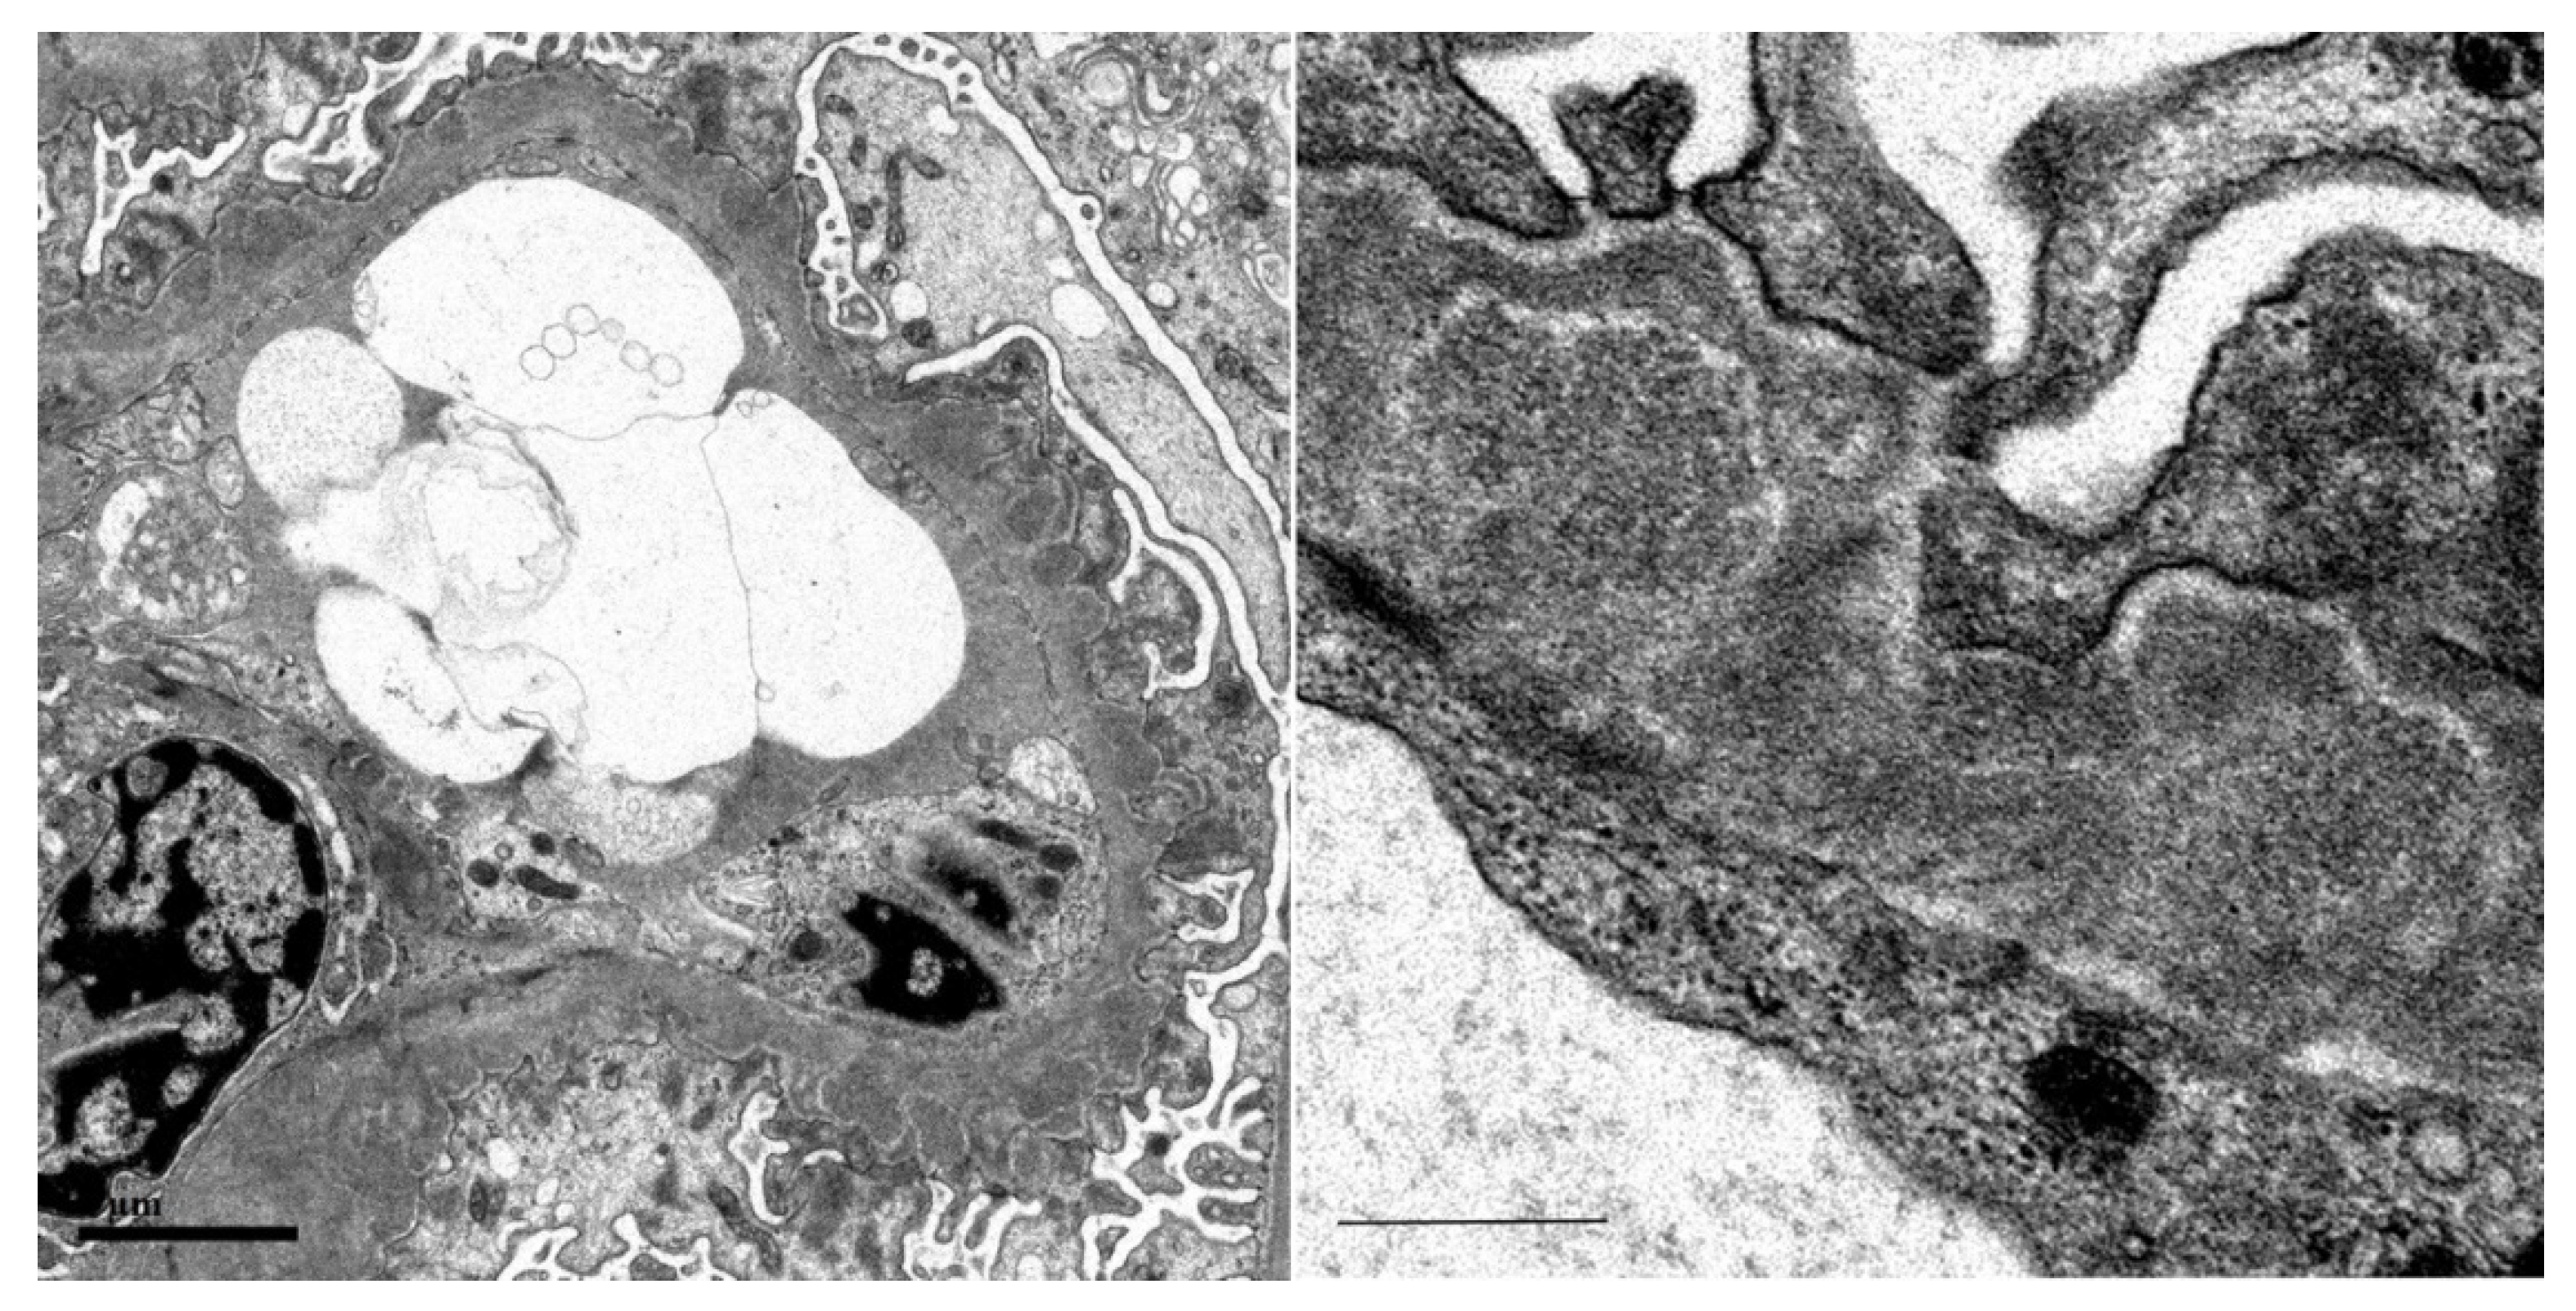

Among the IgG subclasses, IgG1 was the strongest, IgG3 was mildly stained (Figure 2), and immunofluorescence for phospholipase A2 receptor (PLA2R) was negative (Figure 3A), suggesting secondary membranous nephropathy. Electron microscopy revealed an electron-dense deposit in the subepithelial membrane and partly in the basement membrane, indicating stage II–III membranous nephropathy (Figure 4).

Figure 4. Electron microscopy. The bars indicate 2 μm and 0.5 μm.